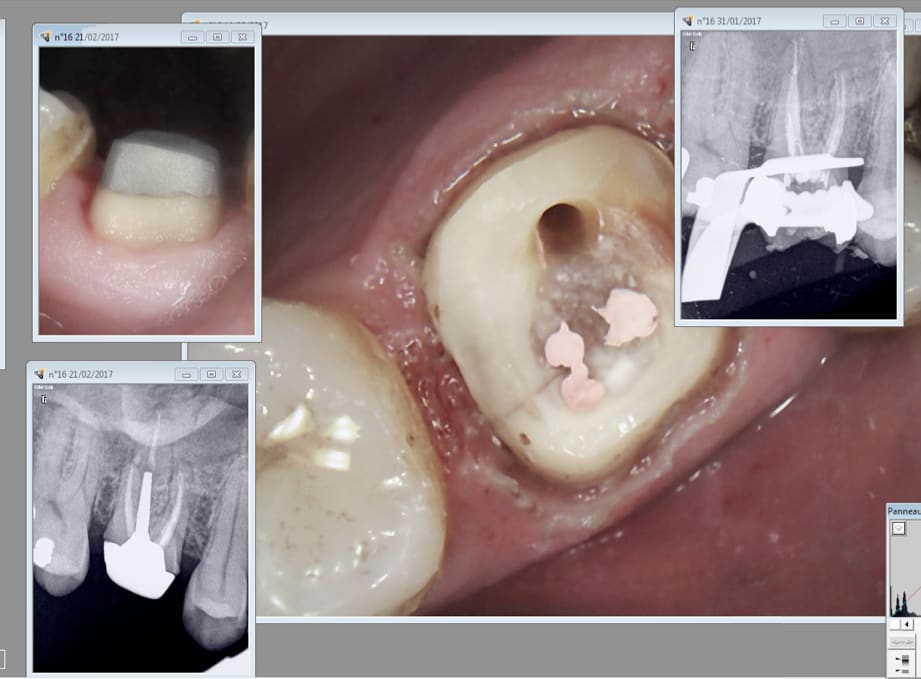

C'est pas la pulpe. Je suis content de ma "fidélisation" surtout quand j'arrive à trouver le MV2 6 ans aprÚs. Comme ca on passe 2 couches de peinture. -)

C'est la pulpe, c'est la pulpe.

Pas de réponse au froid. Curieux non ? -)))

C'est la pulpe c'est la pulpe.

Festival aujourd'hui ! -)))